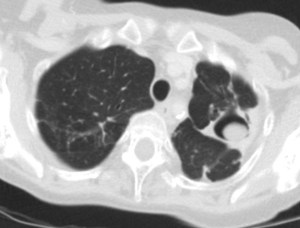

Otro ejemplo del signo del halo (flecha).

Este magnífico ejemplo de signo del halo corresponde a un paciente con metástasis de angiosarcoma. Mi agradecimiento a la sección de radiología tórax de mi hospital (Dra. Maribel Padín y Dra. M. Carmen Aguilar) y a Kiko Padilla, que hizo una lectura perfecta del caso.